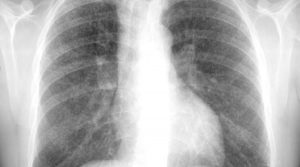

Silicosis_simple